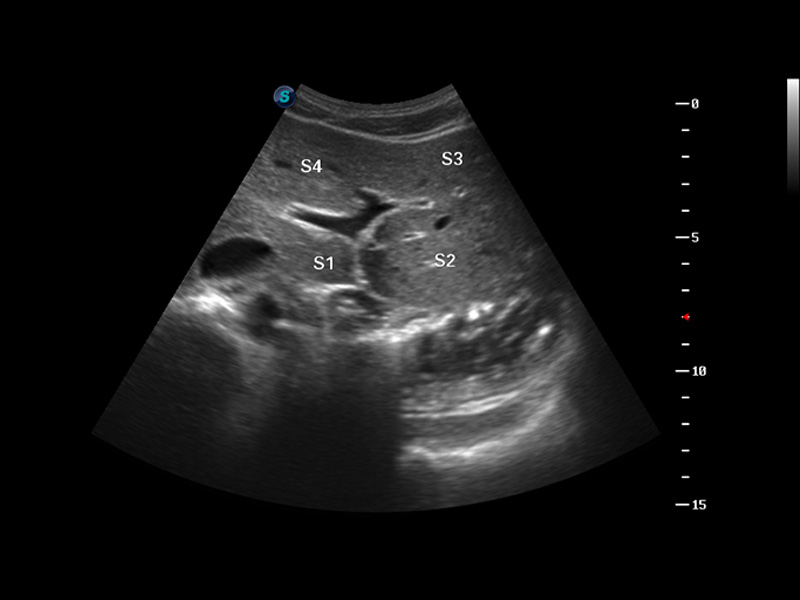

S8 EXP便携式彩色多普勒超声诊断仪是开立医疗研发的高端全身应用型便携彩超。高通道的VIS平台融合可视化(Visual)、智能化(Intelligent)和人性化(Smart)的特点,配以开立医疗自主研发生产的探头大家族,使您能够快速、准确的获得病人信息,提高工作效率的同时减轻疲劳。

成像技术

多波束形成器